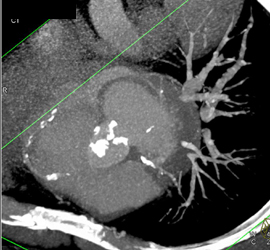

Calcified Bicuspid Valve